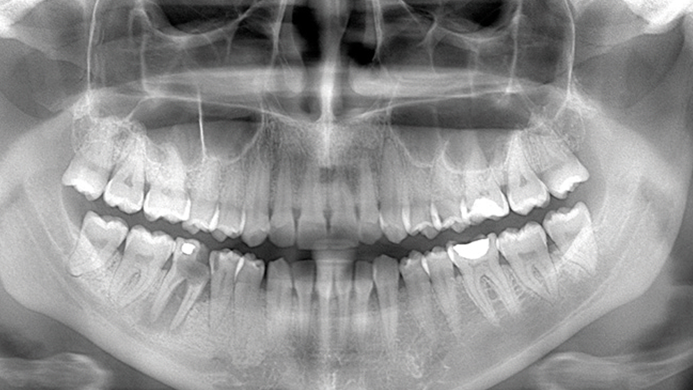

Clinical case: Delayed implant placement: sinus floor elevation by means of lateral

approach & implant placement with GBR

- Courtesy of Dr. Irfan Abas, Netherlands -